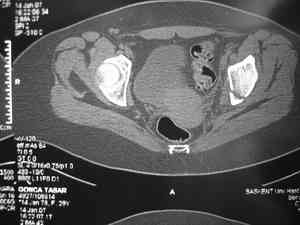

прилагаю пример с такой же давностью травмы, репонировали аппаратом

> в аппарате или одномоментно открыто. Лично я склоняюсь к аппаратному лечению на первом этапе.

задача непростая, если мало опыта в этом деле, подумайте еще раз